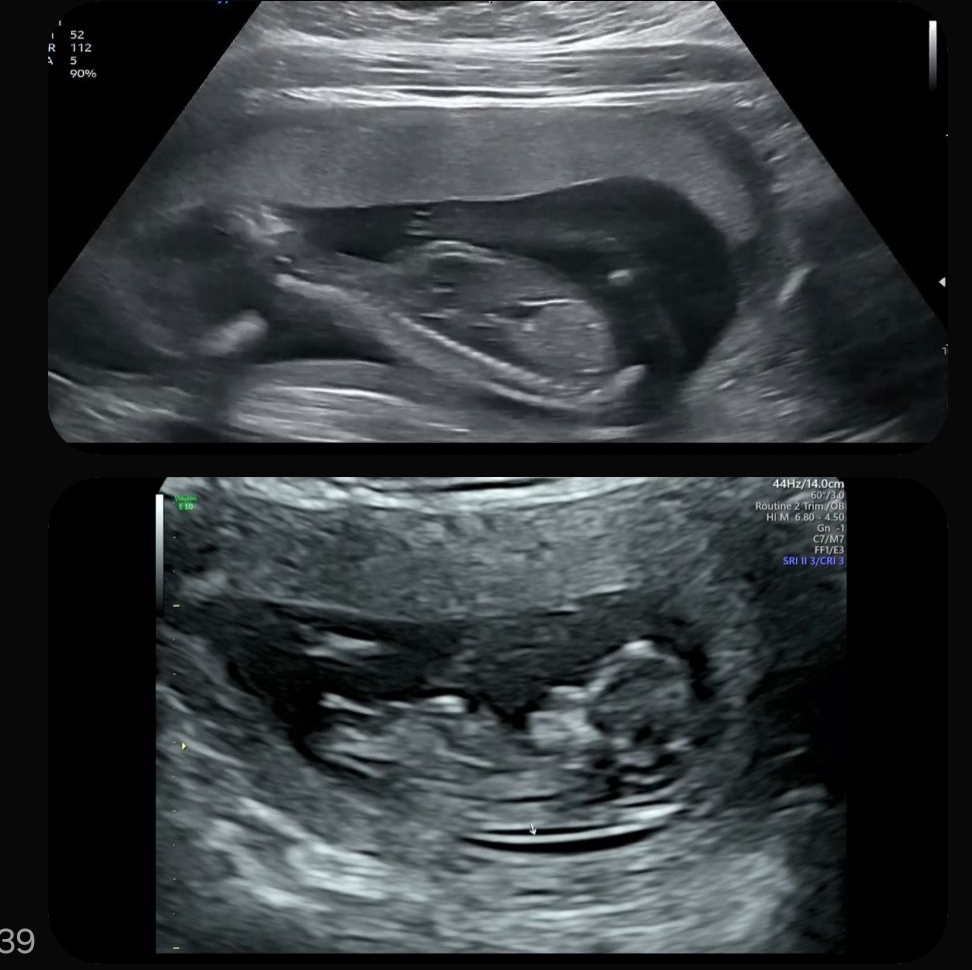

♧성별♤ 16주차인데 병원에서 성별 더 기다려봐야된다고...

16주차인데 병원가기전날부터 성별 기대하고 갔는데 병원에서좀더 기다려보자고해서 김이 팍새네요ㅠ 혹시 병원가서 초음파로 성별만 볼라고하는데 볼수있나요? 위에가 16주고 아래가 14주차때입니다 혹시 잘보시는분 있으면ㅠ